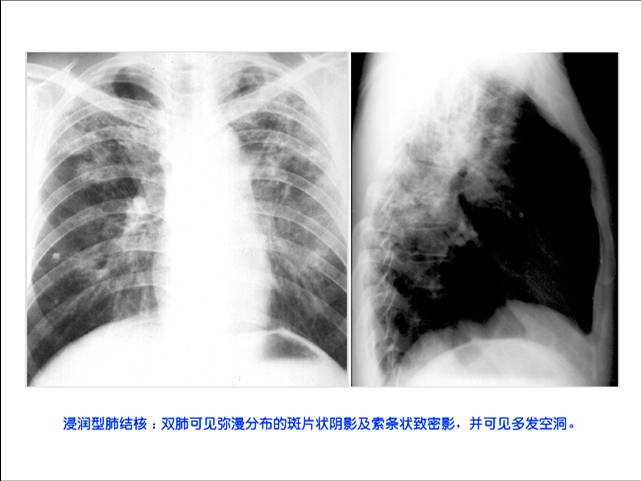

照片名称:浸入性肺结核

照片名称:慢性纤维空洞性肺结核

照片名称:干酪性肺炎